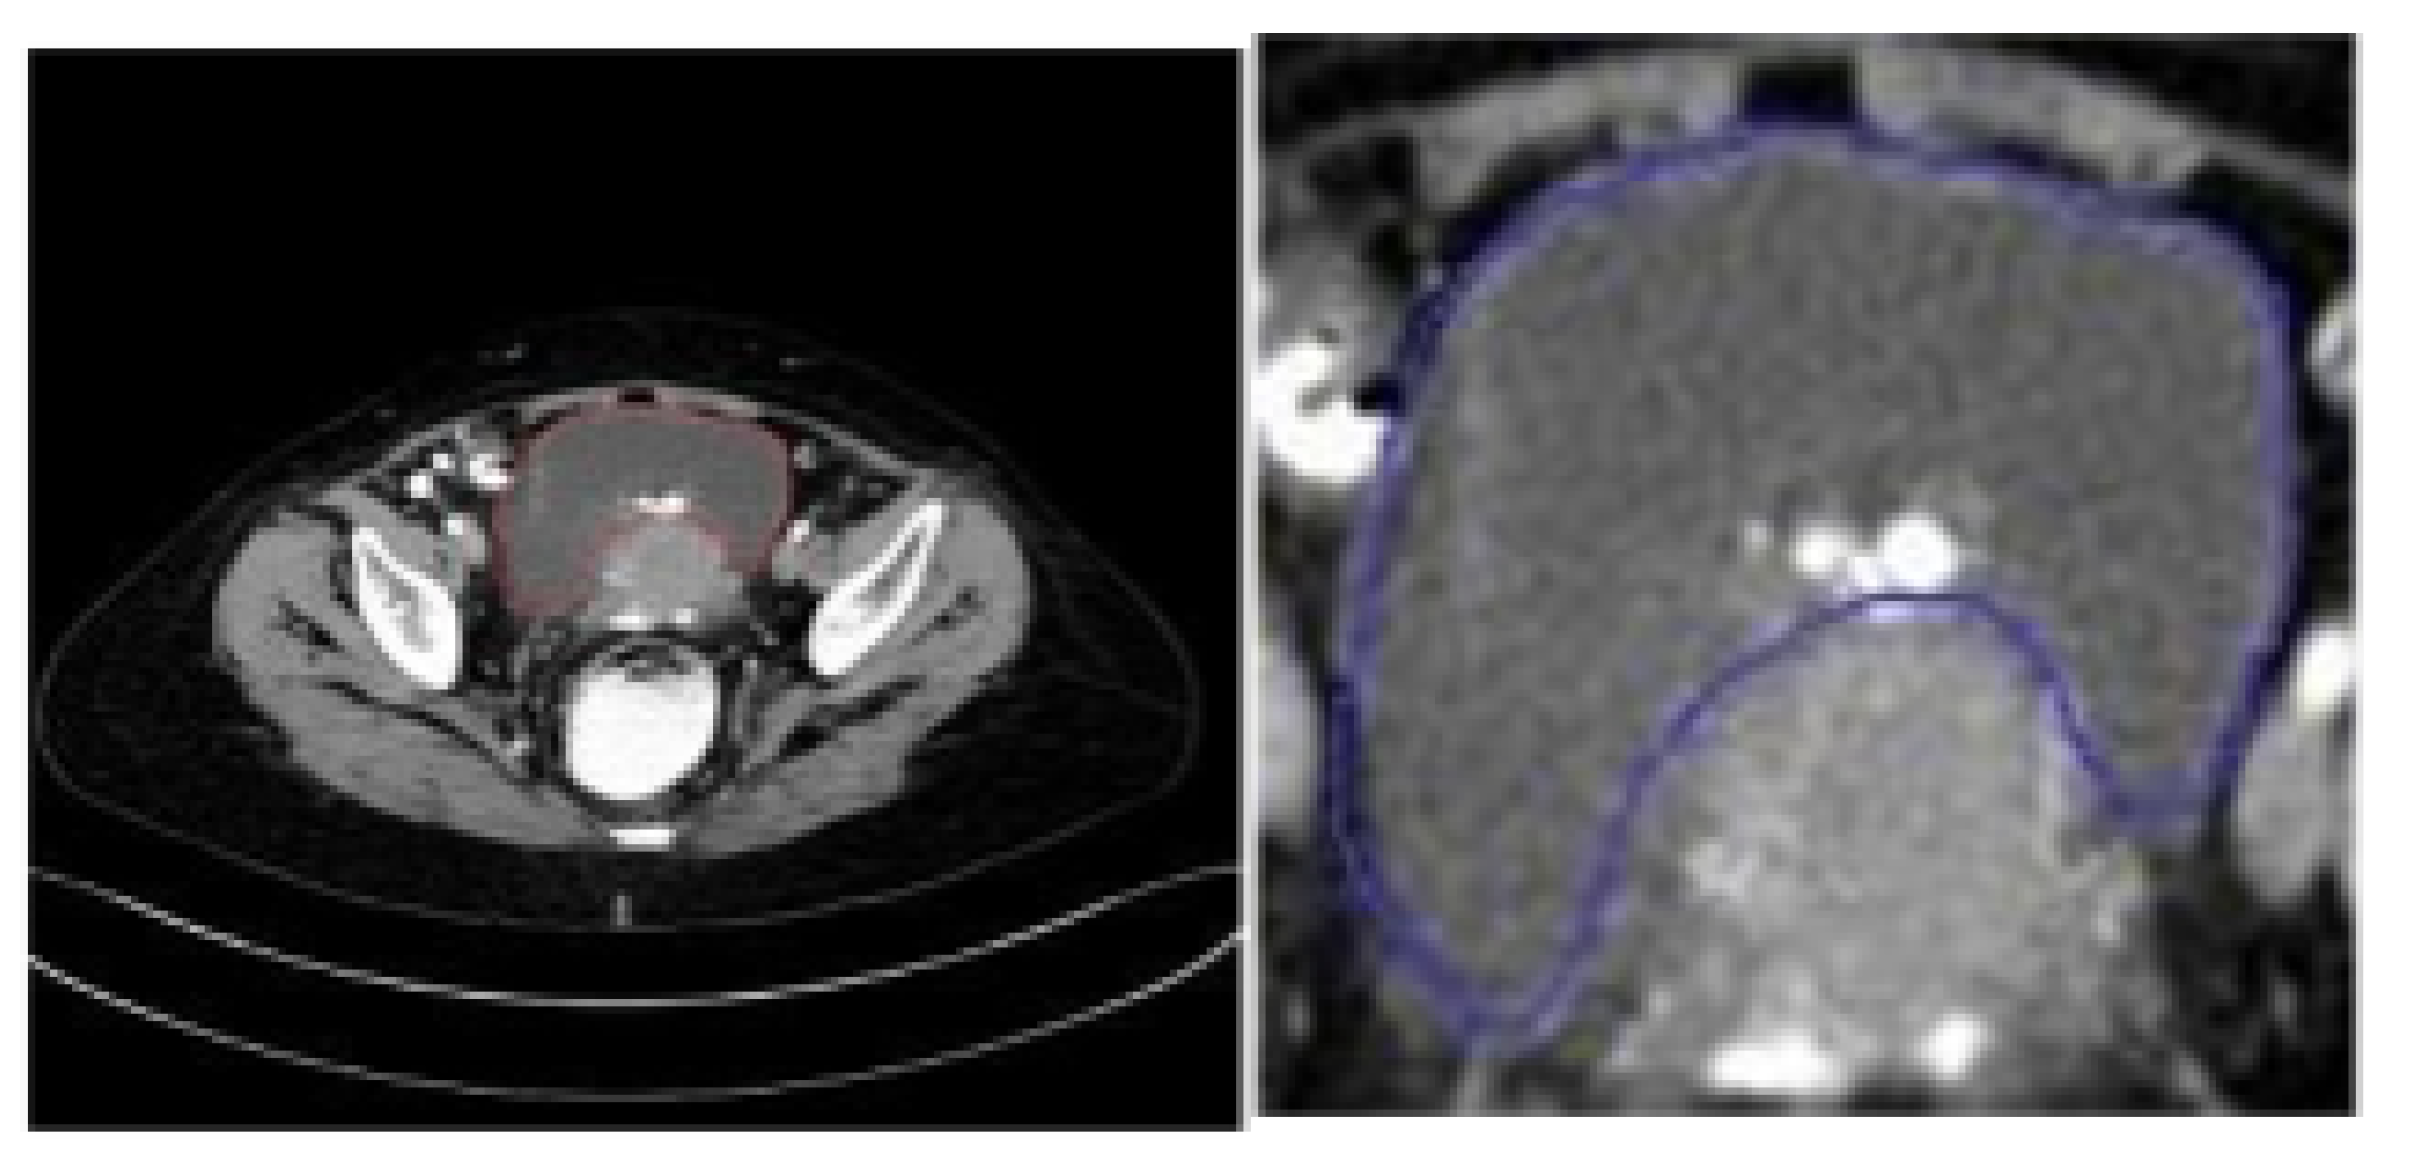

5.1. Data Source and Description

5.2. Data Preprocessing and Dataset Preparation for Training and Evaluation